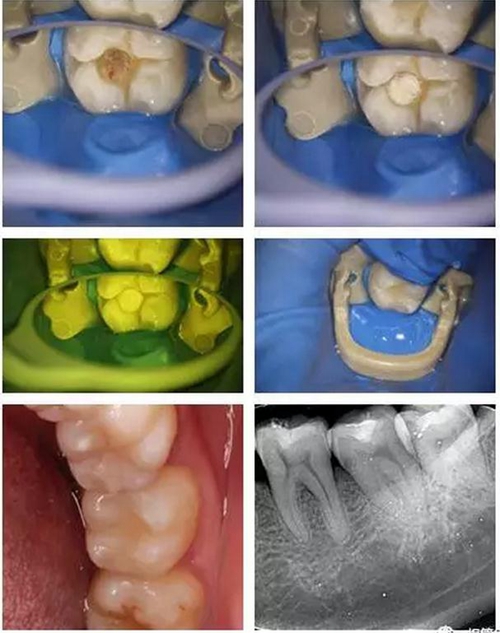

顯微鏡下非常精確與清晰的去凈齲壞組織,精細(xì)的操作盡最大程度保留剩余健康牙本質(zhì),這也需要醫(yī)生精湛的技術(shù)!

6.jpg

所以當(dāng)蛀牙的最前沿非常接近牙髓(比如小于0.5mm時(shí))或者已經(jīng)穿通牙髓時(shí),醫(yī)生在顯微鏡下可見透紅或者出血點(diǎn)時(shí),細(xì)菌就可能已經(jīng)入侵到牙髓組織,這時(shí)即便在我們沒有自覺疼痛癥狀時(shí),保髓的難度和風(fēng)險(xiǎn)就急劇加大了。這時(shí),醫(yī)生需要結(jié)合患者的臨床癥狀、體征以及術(shù)中所見等來綜合決定患牙牙髓的保存與否以及如何保髓了。

8.jpg

(這就是一個(gè)直接穿髓以后,喻剛醫(yī)生根據(jù)情況決定保髓的成功病例,不過這里要非常感謝現(xiàn)在我們擁有的一些新型的生物材料,大大提高了我們保髓治療的成功率!)

9.jpg

美學(xué)樹脂分層堆塑,還原本真!

10.jpg